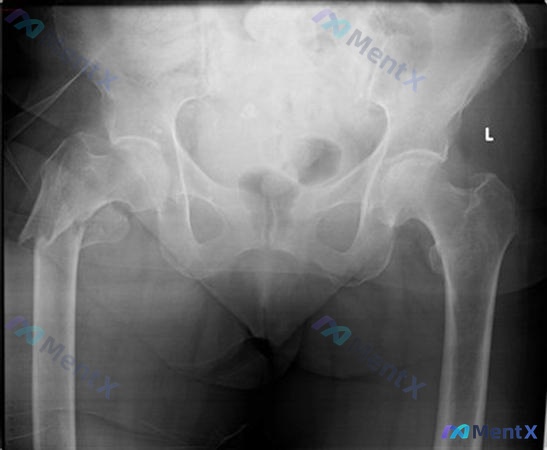

整理到一个骨科病例,有点意思,也有容易被带偏的地方,发出来大家讨论一下。 基本情况: 64岁女性,身体整体健康。 核心病史: 6个月前做了后路右全髋关节置换术(THR),术后到现在已经出现3次后脱位,每次都需要去手术室在麻醉下做闭合复位才能回去。 影像资料: 提供了一张骨盆正位X光片(图A)。 影像...